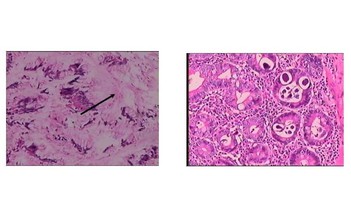

Người phụ nữ mất 4 năm đi chữa trị mới tìm ra nguyên nhân ung thư